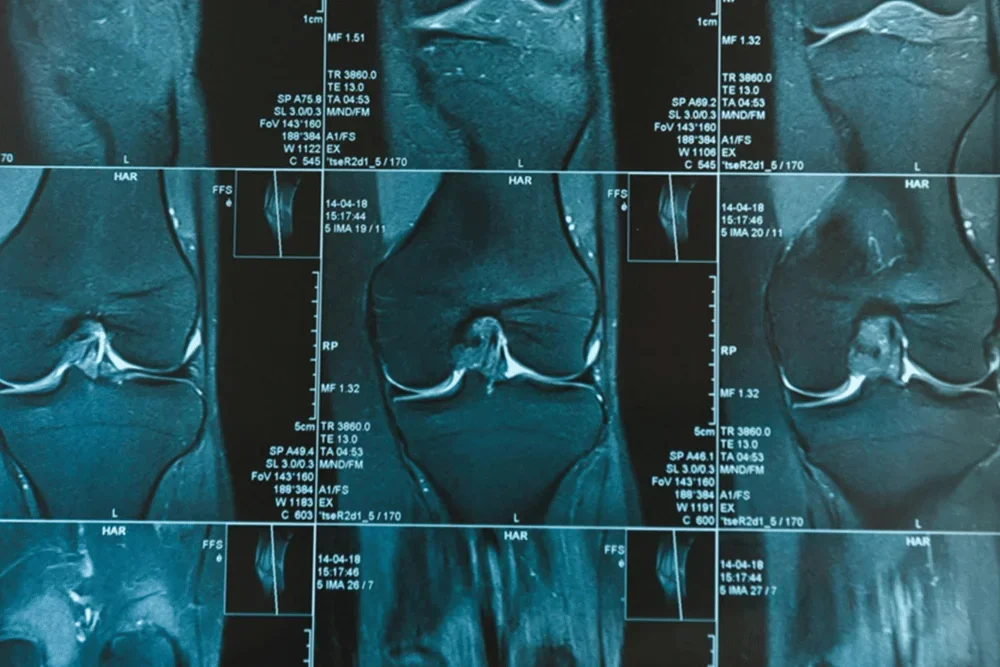

La Resonancia Magnética de Rodilla es una técnica de diagnóstico por imágenes que nos permite obtener una imagen detallada y precisa de la articulación de la rodilla. Este estudio se emplea para evaluar lesiones en ligamentos, meniscos y tejidos circundantes, así como en el diagnostico de problemas en la articulación, como artritis, tendinitis o bursitis, planificación de cirugías y vigilancia de padecimientos crónicos.